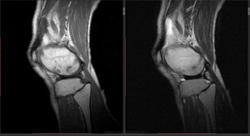

Мужчина 1963 г.р. Жалуется на боль в левом коленном суставе около 6 мес, в последний месяц стало совсем тяжко. Со слов заболел зимой, когда во время прогулки коленки сильно замерзли. Сам думаю на асептический некроз, но смущает множественность поражения.

Дмитрий, я в заболеваниях суставов не дока, но трабекулярный отек вкупе с выпотом может быть обусловлен воспалительными изменениями , но полностью начальные проявления аваскулярного некроза не могу отрицать.

я бы не поставил аваскулярный некроз. если исключена травма, дифференцировать с артритом.

Хрящ не поврежден, для артрита...